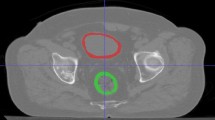

Rectal toxicity is one of the common side effects after radiotherapy in prostate cancer patients. Radiomics is a non-invasive and low-cost method for developing models of predicting radiation toxicity that does not have the limitations of previous methods. These models have been developed using individual patients’ information and have reliable and acceptable performance. This study was conducted by evaluating the radiomic features of computed tomography (CT) and magnetic resonance (MR) images and using machine learning (ML) methods to predict radiation-induced rectal toxicity.

Seventy men with pathologically confirmed prostate cancer, eligible for three-dimensional radiation therapy (3DCRT) participated in this prospective trial. Rectal wall CT and MR images were used to extract first-order, shape-based, and textural features. The least absolute shrinkage and selection operator (LASSO) was used for feature selection. Classifiers such as Random Forest (RF), Decision Tree (DT), Logistic Regression (LR), and K-Nearest Neighbors (KNN) were used to create models based on radiomic, dosimetric, and clinical data alone or in combination. The area under the curve (AUC) of the receiver operating characteristic curve (ROC), accuracy, sensitivity, and specificity were used to assess each model’s performance.